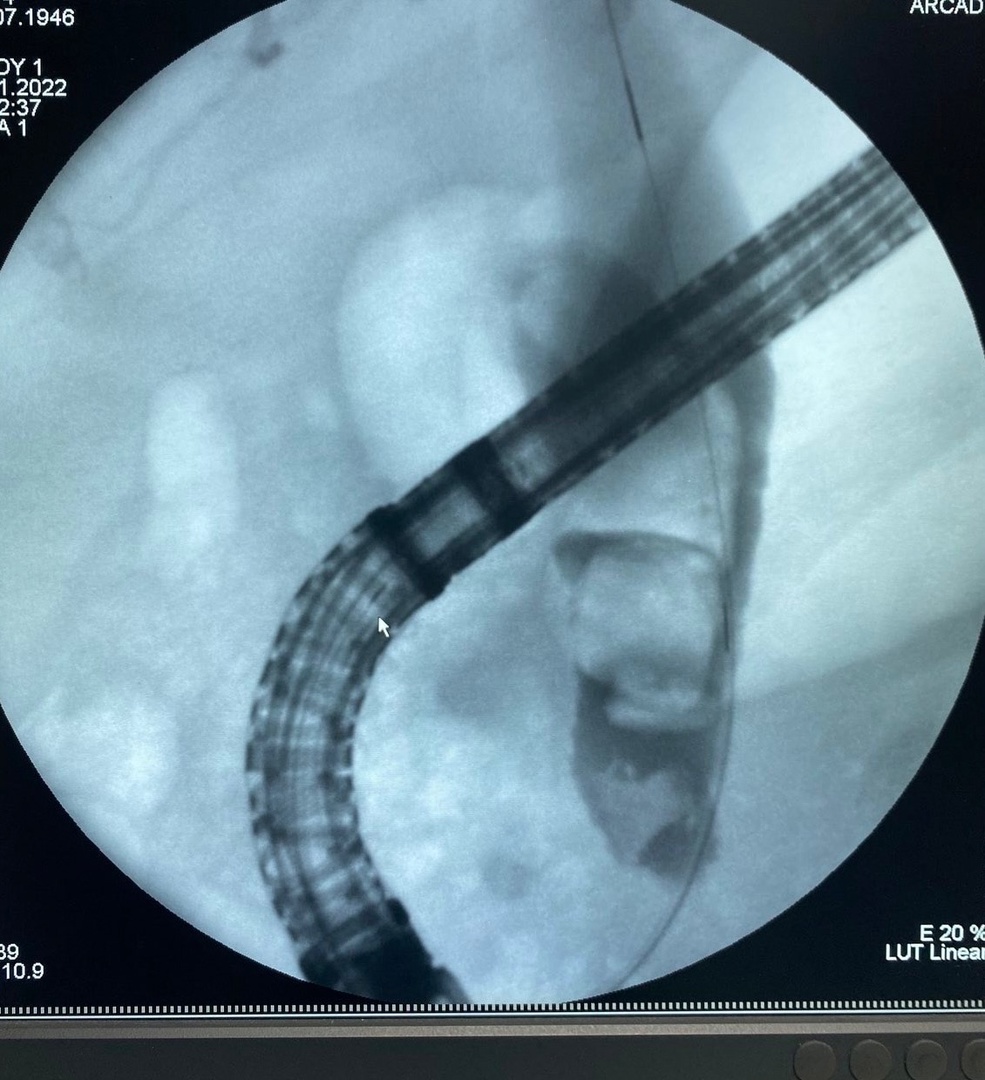

Так, 2 ноября была проведена эндоскопическая операция, во время которой были извлечены 3 желчных камня диаметром 8 мм, 12 мм, 16 мм. Но, к сожалению, в просвете желчных путей остался желчный камень диаметром 22мм, который невозможно было извлечь, не повредив стенку желчного протока. Решением консилиума врачей в составе оперирующего врача - эндоскописта, лечащего врача хирурга, врача анестезиолога и уролога было решено провести попытку лазерного разрушения крупного камня ОЖП (лазерной литотрипсии). Данный метод применяется в крупнейших хирургических клиниках России.

Уже 8 ноября, после небольшой медицинской паузы, которая позволила подготовить пациента к данной операции, операционная бригада в составе 3-х врачей - эндоскопистов: Дашацыреновой Д.Б. Голышевой И.А., Тунгриковой Г.Б., врача уролога - Данилова В.С., операционной м/с Будаевой Э.Б; врача анестезиолога - Галанова Э.Б., медицинской сестры - анестезиста – Захаровой Т.А., впервые в истории панкреато-билиарной хирургии Республики Бурятия была проведена лазерная литотрипсия крупного желчного камня, который далее эндоскопическими инструментами по мелким частям был полностью извлечен из желчных путей пациентки.

Данный метод был впервые успешно применен в Республике Бурятия. Благодаря современному оснащению - лазерному литотриптору фирмы Boston Scientific, эндоскопическому операционному оборудованию, опыту оперирующих врачей - эндоскопистов, уролога, врача анестезиолога, - первая лазерная литотрипсия крупного холедохолитиаза желчных путей - прошла успешно.